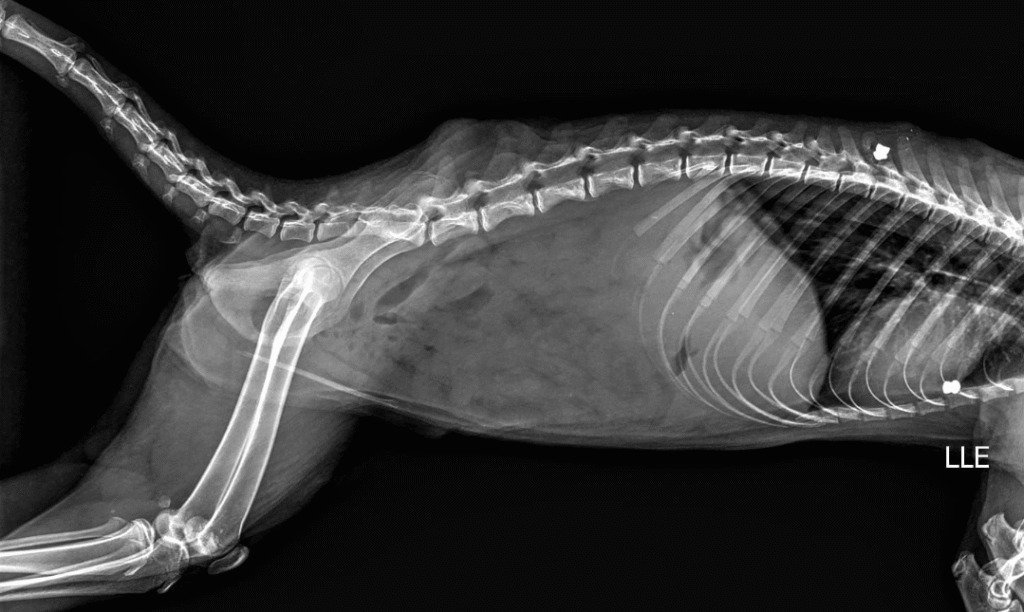

Além da preocupação ambiental, a Secretaria alerta para casos de maus-tratos registrados na região. Há relatos de quatis atingidos por disparos de espingarda de chumbo, incluindo uma fêmea com projéteis alojados no corpo, inclusive na região da coluna vertebral. Um dos casos está sendo acompanhado pela médica veterinária do Bosque Municipal, Dra. Melissa Campitelli, que, após exame de raio-x, identificou dois chumbinhos alojados no corpo de um dos animais.

Radiografia mostra que estão sendo vítimas de maus-tratos na região